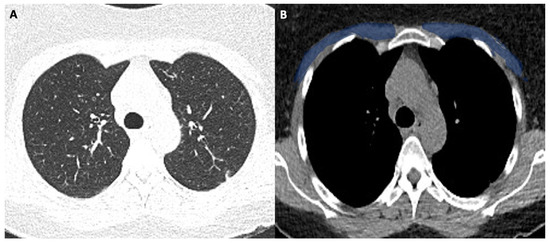

Figure 1 shows the modality of PMD and PMA evaluation. Figure 2 and Figure 3 show the examples of two patients enrolled in the study.

Figure 2A shows the CT image with lung window (pneumonia severity index score: 5). Figure 2B shows the corresponding level in the mediastinal window with high pectoral muscle area (blue area). The patient had a long ICU stay, and he had successful extubation.

Figure 2. (A,B) 58-year-old female with COVID-19.